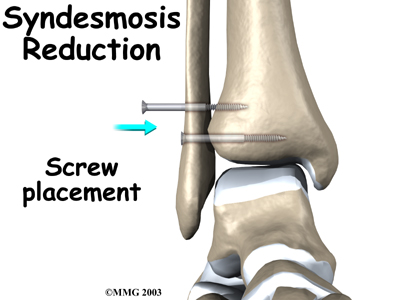

Screw Fixation

Surgery for a syndesmosis injury is designed to reduce the separation between the tibia and fibula. If there are no barriers keeping the tibia and fibula apart, the surgeon may simply need to place screws through the two bones to hold them together while the ligaments heal.

To begin the procedure, the surgeon bends the ankle slightly upward. A clamp may be placed around the lower leg to squeeze the tibia and fibula together, reducing the separation. This places the two bones in the proper alignment.

Working from the outer side of the leg, the surgeon inserts a screw through fibula into the tibia. This is done with the aid of a fluoroscope. A fluoroscope is a special X-ray machine that allows the surgeon to see the live X-ray picture on a TV screen during surgery. Using the fluoroscope allows the surgeon to direct the drill and place the screws into the right spot to hold the bones in the right position. This can usually be done through small, quarter-inch incisions in the side of the ankle. Some surgeons place a second screw right above the first screw.

Surgeons generally use a screw with a large head. This ensures easy removal of the screw after two or three months.